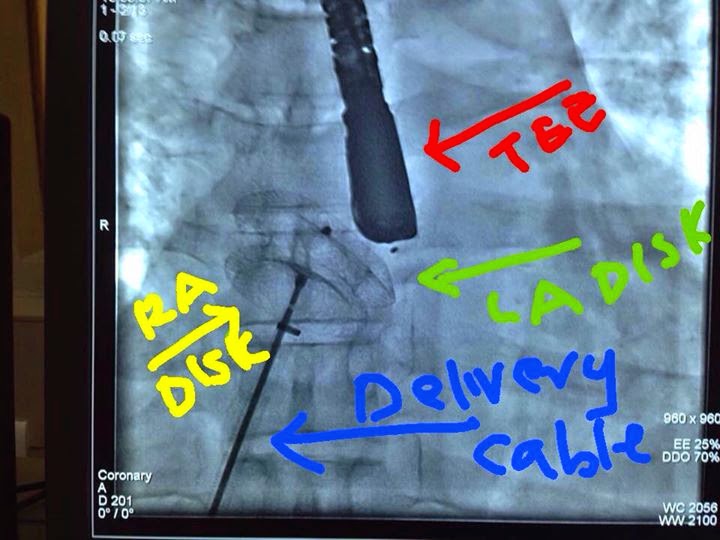

From drsvenkatesan.com